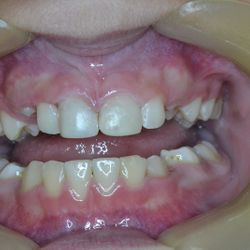

Το χαμόγελο της μικρής ασθενούς μας αποκαταστάθηκε άμεσα όπως είναι εμφανές στην τελευταία φωτογραφία.